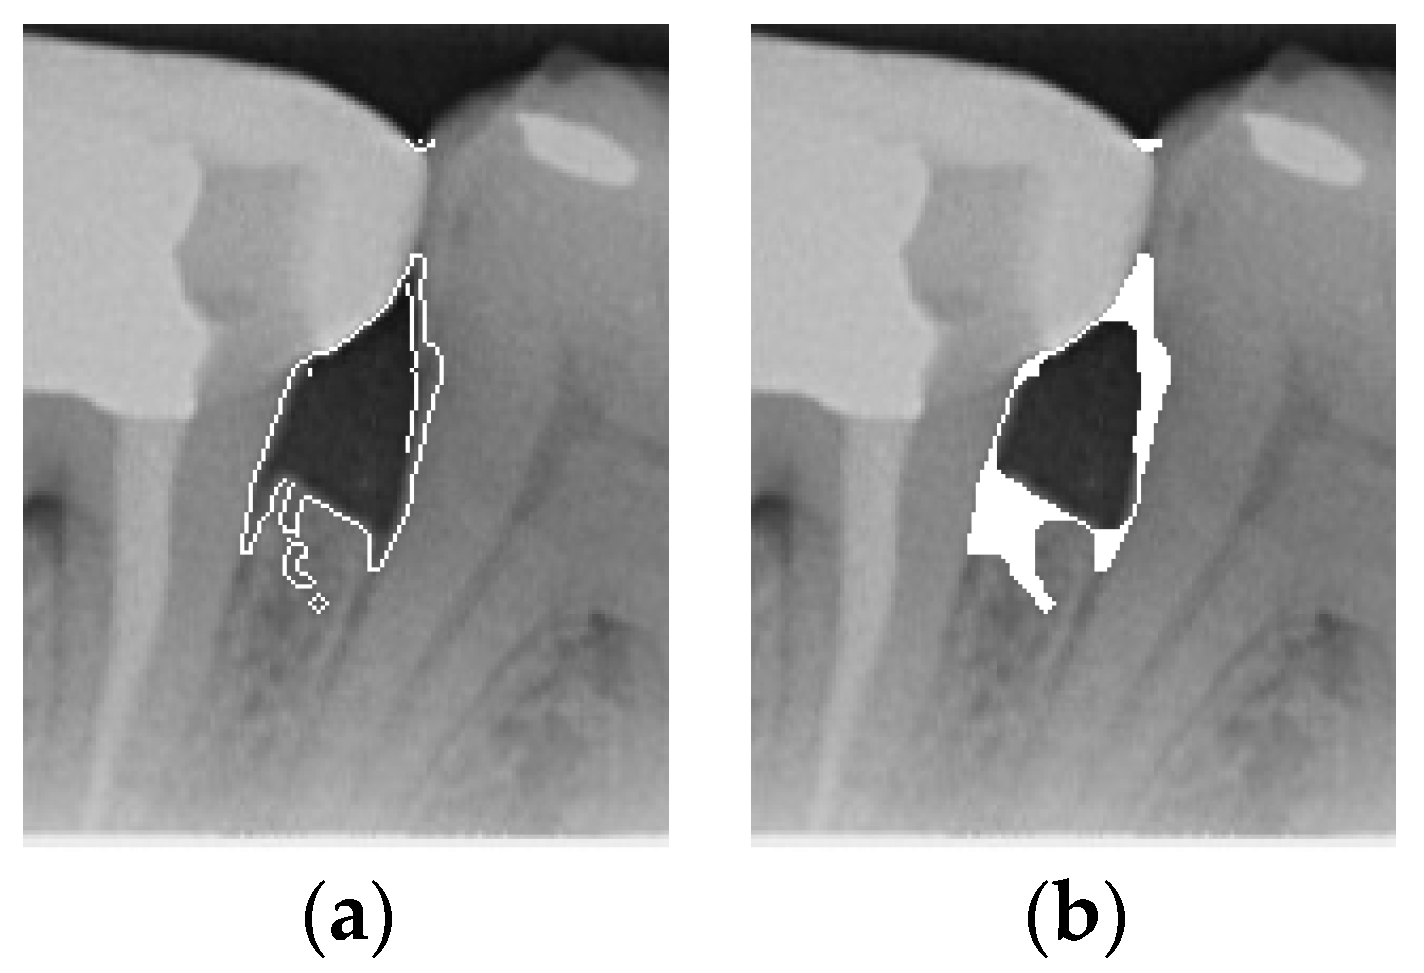

To ensure that only the area framing the symptom is preserved, and to remove the rest of the interfering areas or lines, the symptom frames are extracted according to the closure algorithm, i.e., the maximum connectivity area can be preserved to remove the frames of the non-symptomatic areas, as shown in Figure 7b. After the closure process, some of the frame lines are less smooth than others, which may affect the discrimination accuracy. To deal with this situation, this study performs the filling of the frame lines at the symptom area to facilitate the training of the model. Black and white are chosen to highlight the contrast and to compare the difference in discrimination between the two fill colors, as shown in Figure 7c,d.

Figure 7. Comparison of extracting the closed area and filling. (a) Close operation. (b) Extracting the closed area. (c) Filling with white. (d) Filling with black.